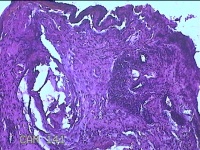

右侧肘后包块

性别

男

年龄

59岁

临床诊断

脂肪瘤

一般病史

发现右侧肘后包块1年余,无明显疼痛及不适。

标本名称

大体所见

灰白暗红色肿物1.3x0.5x0.3cm一个,表面糜烂。